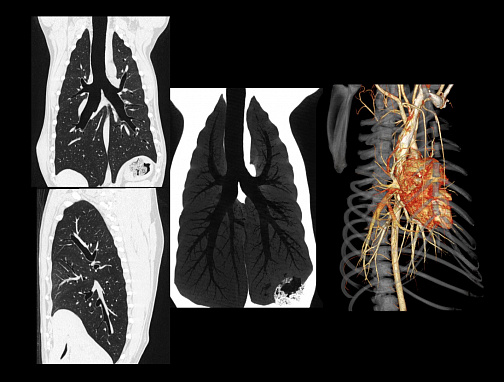

SinoVision AlphaCT 358 Plus — компьютерный томограф на 64 среза. Устройство позволяет получать изображения высокой чёткости с помощью современной интеллектуальной платформы.

Универсальный томограф AlphaCT 358 Plus позволяет получать изображения высокой чёткости.

Виртуальная эндоскопия, позволяющая воссоздать внутреннюю структуру полых органов животных, что может быть актуально, например, при планировании предстоящей операции.

• Интеллектуальная система обработки изображения

• Патентованный детектор V-PIXEL